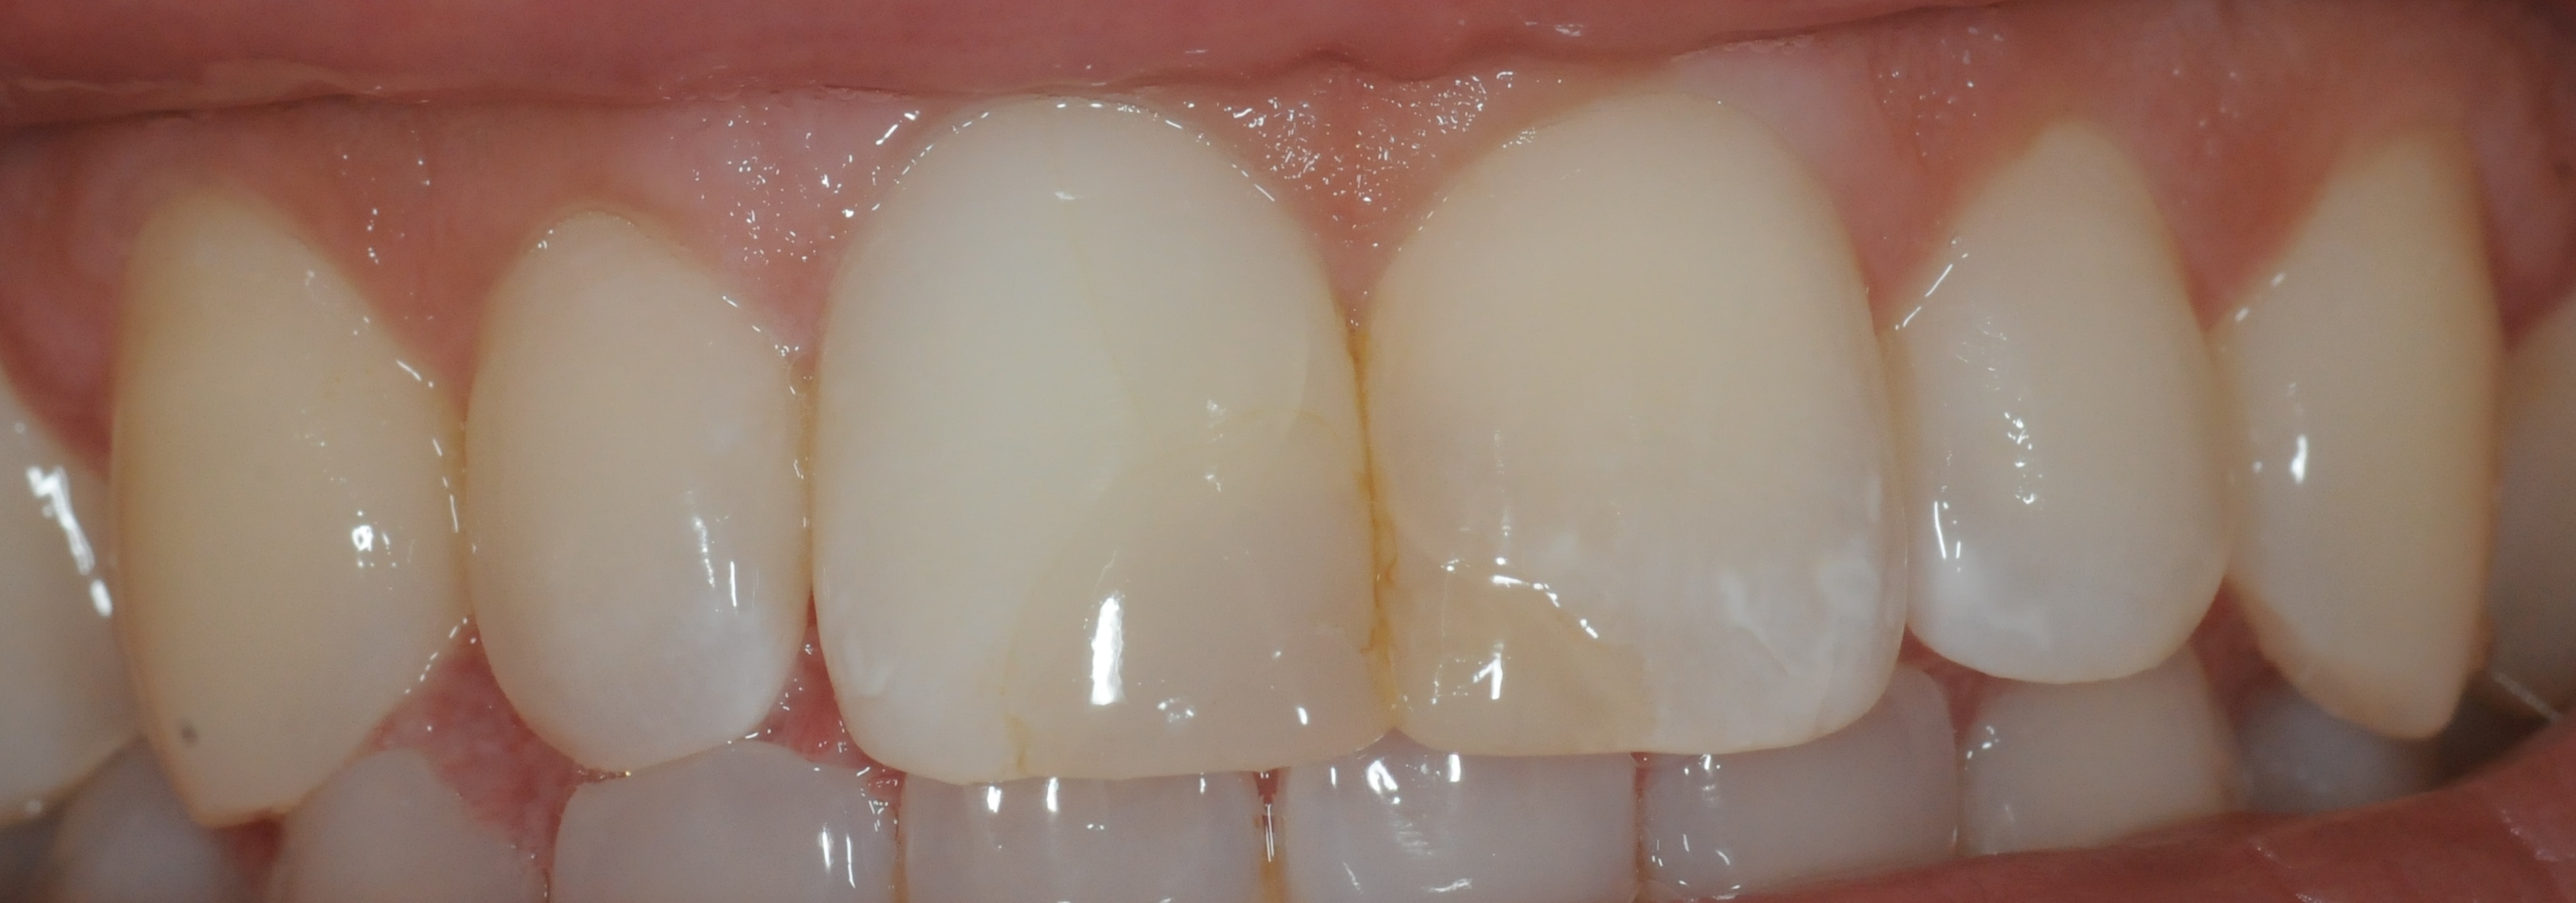

Zustand nach einer Woche Bleicheinlage. Der Zahn kann nun mit einer definitiven Füllung versorgt werden.

Es wird auch oft gefragt, wie lange denn der Bleicheffekt anhält. Beim Bleichen werden Farbstoffe, die sich in den Zahn eingelagert haben optisch inaktiviert. Danach sollten eigentlich keine weiteren Farbstoffe mehr da sein, somit sollte das Bleichergebnis dauerhaft sein. Wir haben mittlerweile Langzeitergebnisse von über 17 Jahren. Das Ergebnis hat sich nicht verändert.

Hier ist aber auch deutlich zu sehen, was Internes Bleichen (Bleaching) nicht kann: vorhandene Füllungen bleiben wie sie sind und kommen durchs Bleichen stärker zur Geltung. Diese müssen dann gegebenenfalls getauscht werden, um die Farbe an den gebleichten Zahn anzupassen. Das gleiche gilt für Verfärbungen als Auflagerungen auf dem Zahn, diese werden im Rahmen der Zahnreinigung wegpoliert.